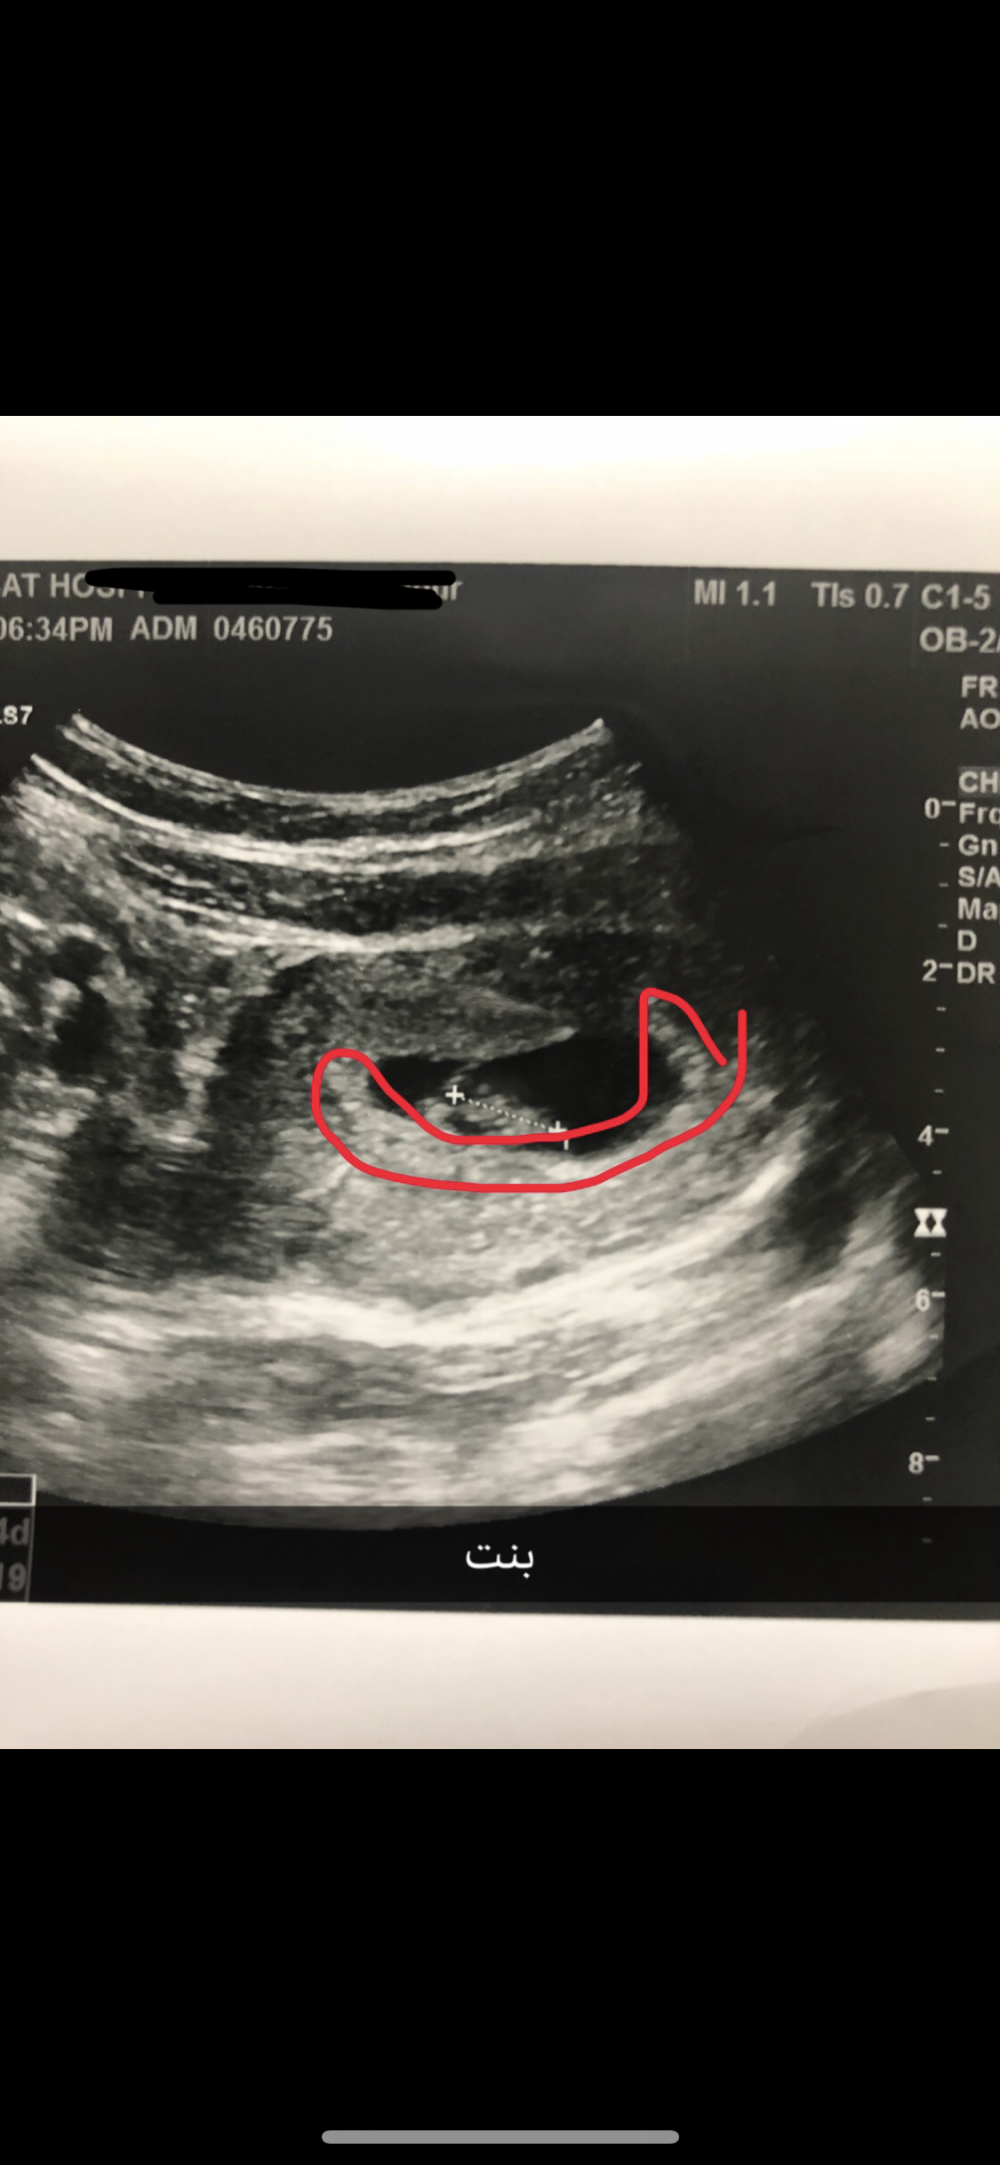

هذي صورة سوناري